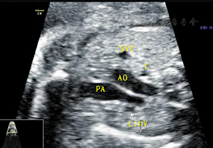

孕妇31岁,孕27+1周,产前常规行胎儿超声心动图检查。既往体健,无传染病及遗传病史,孕期顺利。超声显示:胎儿心脏位于胸腔内,位置正常,心尖指向左前方。心轴及心胸比值正常。各心腔内径比值正常,室壁厚度及运动正常。各瓣膜形态及启闭未见明显异常,彩色多普勒血流显像未见异常血流信号。三血管–气管切面:肺动脉左侧可见管状回声,内径0.21 cm(图1),探头于该切面向胎儿头侧偏转,可见其跨越右肺动脉上方,于主动脉弓下方从左向右径直走行,在距上腔静脉右心房入口约0.61 cm处汇入其中,其内可见静脉频谱(图2)。主动脉弓长轴切面:主动脉弓下方可见两个管状回声,呈"双眼征",其中前下方为右肺动脉横断面,后上方为异常血管断面;彩色多普勒示二者血流方向相反(图3)。余切面未见明显异常。心律规整,心率148次/min。超声提示:胎儿左无名静脉走行异常(主动脉弓下走行)。产后经超声及心血管造影证实。

在胚胎发育的第7周,左、右两侧的前主静脉借血管丛连接成一条斜行的血管,即无名静脉。随着左无名静脉发育形成后,左侧前主静脉和Cuvier管逐渐闭塞,左上腔静脉退化,右侧前主静脉与Cuvier管发育成为正常的右上腔静脉[1]。左、右无名静脉分别接收左、右颈总静脉和左、右锁骨下静脉的静脉血,汇总成上腔静脉,自右房上面注入右房。正常情况下,左无名静脉由左向右斜行跨过主动脉弓上方,汇入上腔静脉。但本例中,三血管–气管切面向胎儿头侧偏转动态扫查显示左无名静脉在主动脉弓下方与右肺动脉上方之间横过主动脉弓,在上腔静脉入右心房处同上腔静脉汇合;主动脉弓长轴切面也可显示主动脉弓与右肺动脉间存在一圆形静脉血管结构,而正常情况下,主动脉弓下仅有右肺动脉的横断面;三血管–气管切面肺动脉左侧可见一管状回声,为静脉频谱,这是由低位走行即主动脉弓下走行的左无名静脉所致。关于三血管–气管切面肺动脉左侧发现异常管状回声,有以下三种可能:①永存左上腔静脉Ⅰ型,左上腔静脉血经冠状静脉窦入右房,此型约占90%以上。超声表现:四腔心观左房室沟交界处见扩张的冠状静脉窦;三血管切面肺动脉左侧出现一静脉血管,呈"四血管"改变,且该静脉频谱与右上腔静脉频谱或肺静脉频谱相似;旋转探头,发现该静脉与冠状静脉窦相连且血流方向与右上腔静脉相同。②完全性肺静脉异位引流心上型,四腔心观看不到正常回流入左心房的4支肺静脉,左心房后方可见异常血管,为垂直静脉;三血管–气管切面肺动脉外侧可见管状回声,但血流方向与右上腔静脉相反,为上行的垂直静脉,先后汇入左无名静脉及右上腔静脉。③伪像,由于切面偏斜,将左房的一部分也包括在其内,若此时观察到4支肺静脉均回流入左心房,即为伪像所致。排除以上几种情况,特别是排除了严重危及新生儿存活的完全性肺静脉异位引流,本研究即可考虑左无名静脉主动脉弓下走行的可能。综上所述,超声表现为三血管–气管切面肺动脉左侧异常管状回声,主动脉弓长轴下方出现"双眼征",且二者血流方向不同,并且无其他心内外结构异常时可以诊断为左无名静脉主动脉弓下走行。